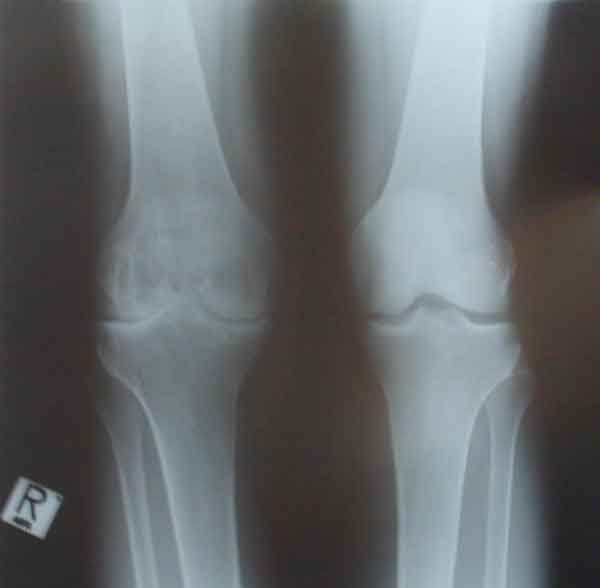

משמאל התמונה צילום רנטגן של ברך ימנית הרוסה לאחר דימומים חוזרים ונישנים, מימין-ברך שמאלית במצב תקין

אותם ברכיים לאחר 15 שנים. שים לב שהסחוס בברך הימנית נשחק באופן קשה-החולה סובל מכאב בכל תנועה של הברך